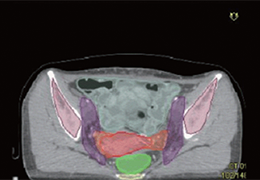

分析智能。

这些功能利用数字控制面板分析运营、业务和临床绩效。

使管理员能够跟踪关键参数,包括平均曝光率、拒绝的影像和探测器统计信息。

帮助确定需要改进的方面,支持为员工和部门制定适当的改进计划。